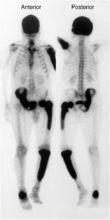

全身多處放射性濃聚灶骨顯像/骨掃描(ECT)

核素骨顯像在Paget’s病有明顯的特徵:受累骨通常有顯著的放射性攝取增加並核素

分布均勻,當有局限性骨質疏鬆時,僅在病灶邊緣表現為強攝取。

典型的Paget’s病骨顯像容易識別,可以用來評價骨骼病變的範圍,單骨還是多骨受累有獨到的優勢,是理想的篩選技術。同時骨顯像比放射檢查有更高的靈敏度,並可以追蹤疾病的進展及治療效果,對檢查前血清鹼性磷酸酶正常的病人,骨顯像是了解治療反應的客觀手段。